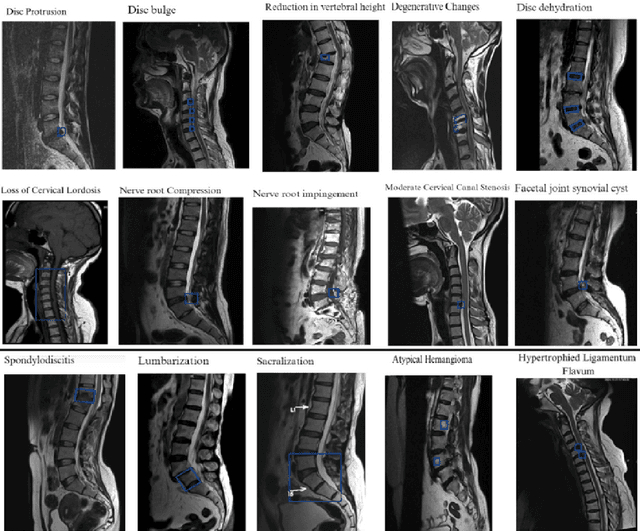

Abstract:Study Design This study presents the development of an autonomous AI system for MRI spine pathology detection, trained on a dataset of 2 million MRI spine scans sourced from diverse healthcare facilities across India. The AI system integrates advanced architectures, including Vision Transformers, U-Net with cross-attention, MedSAM, and Cascade R-CNN, enabling comprehensive classification, segmentation, and detection of 43 distinct spinal pathologies. The dataset is balanced across age groups, genders, and scanner manufacturers to ensure robustness and adaptability. Subgroup analyses were conducted to validate the model's performance across different patient demographics, imaging conditions, and equipment types. Performance The AI system achieved up to 97.9 percent multi-pathology detection, demonstrating consistent performance across age, gender, and manufacturer subgroups. The normal vs. abnormal classification achieved 98.0 percent accuracy, and the system was deployed across 13 major healthcare enterprises in India, encompassing diagnostic centers, large hospitals, and government facilities. During deployment, it processed approximately 100,000 plus MRI spine scans, leading to reduced reporting times and increased diagnostic efficiency by automating the identification of common spinal conditions. Conclusion The AI system's high precision and recall validate its capability as a reliable tool for autonomous normal/abnormal classification, pathology segmentation, and detection. Its scalability and adaptability address critical diagnostic gaps, optimize radiology workflows, and improve patient care across varied healthcare environments in India.